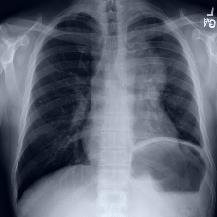

Thoracic disease detection from chest radiographs using deep learning methods has been an active area of research in the last decade. Most previous methods attempt to focus on the diseased organs of the image by identifying spatial regions responsible for significant contributions to the model's prediction. In contrast, expert radiologists first locate the prominent anatomical structures before determining if those regions are anomalous. Therefore, integrating anatomical knowledge within deep learning models could bring substantial improvement in automatic disease classification. This work proposes an anatomy-aware attention-based architecture named Anatomy X-Net, that prioritizes the spatial features guided by the pre-identified anatomy regions. We leverage a semi-supervised learning method using the JSRT dataset containing organ-level annotation to obtain the anatomical segmentation masks (for lungs and heart) for the NIH and CheXpert datasets. The proposed Anatomy X-Net uses the pre-trained DenseNet-121 as the backbone network with two corresponding structured modules, the Anatomy Aware Attention (AAA) and Probabilistic Weighted Average Pooling (PWAP), in a cohesive framework for anatomical attention learning. Our proposed method sets new state-of-the-art performance on the official NIH test set with an AUC score of 0.8439, proving the efficacy of utilizing the anatomy segmentation knowledge to improve the thoracic disease classification. Furthermore, the Anatomy X-Net yields an averaged AUC of 0.9020 on the Stanford CheXpert dataset, improving on existing methods that demonstrate the generalizability of the proposed framework.